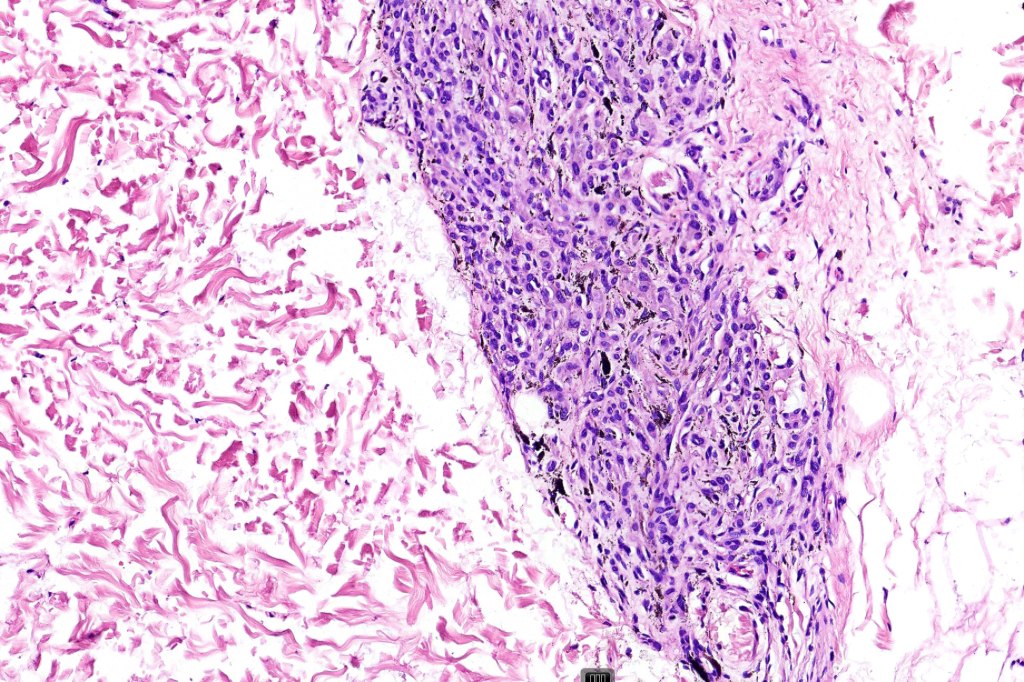

•Symmetrical, circumscribed wedge-shaped infiltrate-most common growth pattern with the broad base uppermost, deeper aspect extends along appendageal structures & neurovascular bundles with a fasciular or plexiform pattern

•Plexiform growth pattern very occasionally seen (plexiform spindle cell nevus (Barnhill)

. Perineural spread sometimes seen, infiltration of arrector pili muscles common

Atypical features which may be encountered include marked nuclear pleomorphism, conspicuous mitotic activity, atypical mitoses (atypical or borderline lesion)- may be associated with lymph node involvement although frank maliganncy is exceptional